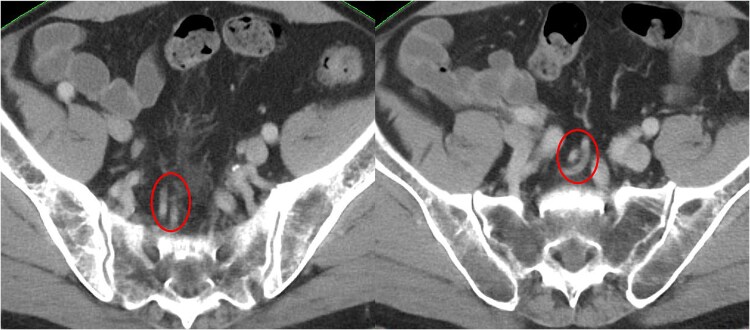

In the last decade, the role of radiotherapy in rectal cancer has changed significantly with the introduction of total neoadjuvant therapy (TNT) and nonoperative management (NOM). For the setting of irradiation field in rectal cancer, the pararectal, lateral lymph nodes, and those along the inferior mesenteric artery (IMA) are most important. In total mesorectal excision (TME), the root of the IMA is dissected. In the atlas of pelvic irradiation for rectal cancer, the setting of the upper margin of the mesorectum varies from atlas to atlas, and no atlas sets the upper margin of the mesorectum to the root of the IMA. In particular, there is no consensus on the definition of anatomical boundaries regarding the lymph nodes along the superior rectal artery (SRA). The upper margin of the irradiation field in clinical trials of preoperative radiotherapy and TNT is generally set at the level of the internal and external iliac artery branches, L5/S1, or S2/S3. However, it is not necessary to include the entire mesorectum to the root of the IMA in patients undergoing preoperative radiotherapy plus TME. Conversely, for patients receiving NOM, the irradiation field may have to include the mesorectum to the IMA root, though the incidence of lymph node metastasis and gastrointestinal adverse events merits consideration. It is increasingly important to determine the extent of clinical target volume around the SRA region and the setting of the upper margin of the irradiation field after formulating the treatment policy together with the surgeons and medical oncologists.